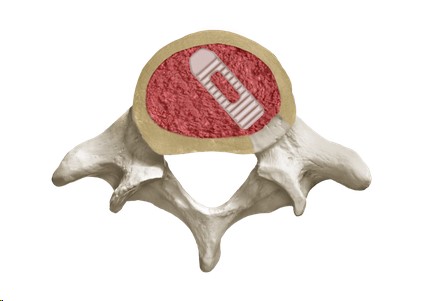

FORTIFY Corpectomy Spacer

FORTIFY I Corpectomy Spacer

FORTIFY VA Corpectomy Spacer